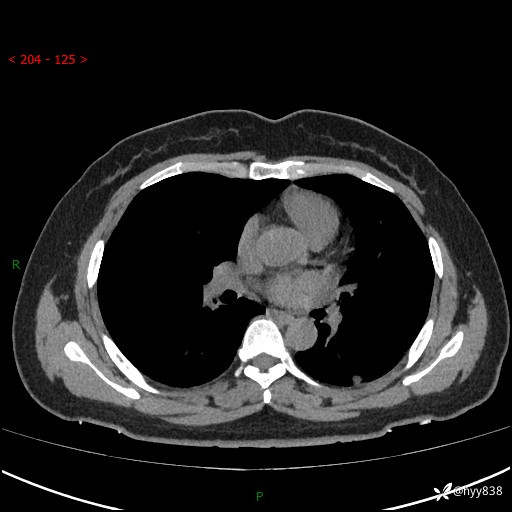

胸部CT平扫(2023.3)